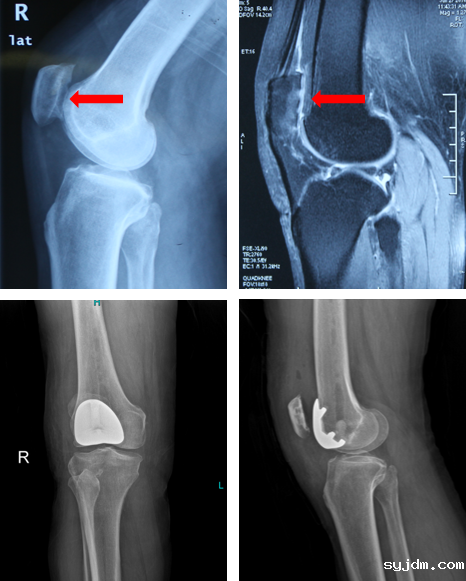

对于病变严重且保守治疗无效的髌股关节炎患者,需考虑进行手术治疗。比如软组织对位重排手术、截骨术,或髌股关节置换术。目前,髌股关节置换术是治疗髌股关节炎的终极手段,但其相对传统的全膝关节置换来说,由于仅对髌股关节病变局部进行了表面置换,因此创伤更小,手术过程中保留了健康的胫股关节、半月板以及韧带等结构,术后也可更快地恢复关节运动功能,让患者更好地受益。

髌股关节置换术前(上图)及术后影像(下图)